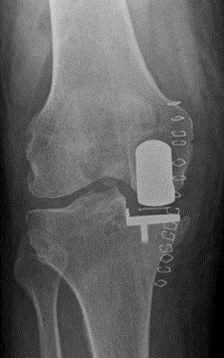

Ms Chloe Scott is a Consultant Trauma and Orthopaedic Surgeon with a specialist interest in hip and knee arthroplasty and lower limb trauma. She has a particular expertise in partial knee replacement surgery, robotic assisted joint replacements and in complex knee replacement surgery including revision.

Ms Scott graduated from the University of Edinburgh medical school in 2004. She completed her orthopaedic training in Edinburgh during which time she also completed higher degrees in Orthopaedic Engineering at Cardiff University and in partial knee replacement design at the University of Edinburgh. She completed travelling fellowships in Boston, Chicago, and South Carolina USA.